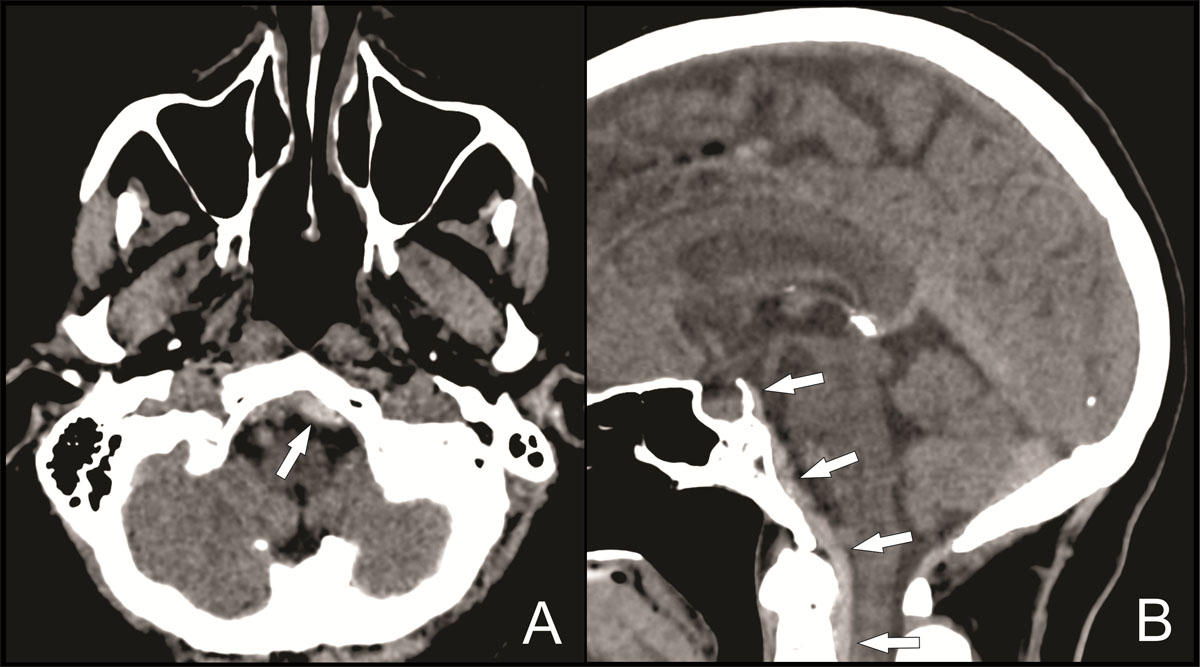

Computed tomography (CT) revealed no skull or cervical spine fractures, but a small subdural hematoma was seen along the left tentorium without significant mass effect (Figure 1, white arrow).

Figure 1

In addition, a hyperdense collection with a maximal thickness of 6 mm was visible posterior to the clivus and descending anteriorly into the foramen magnum (Figure 2A–2B, white arrows), suggestive of an acute subdural or epidural hematoma.

Figure 2